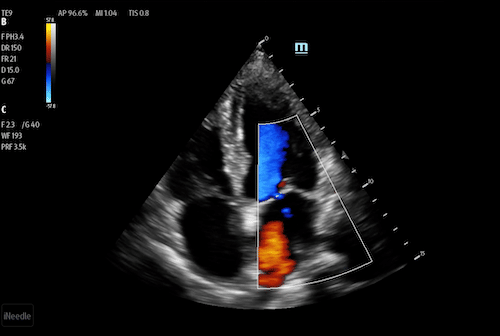

Phased Ultrasound Transducers

A phased transducer has a small footprint with a sector image shape and features high temporal resolution and penetration. This allows clinicians to image structures that are moving in real-time. Phased transducers are most frequently used with applications ranging from cardiac, transcranial, abdomen, and pediatrics.

Apical 4 chamber with color Doppler using a phased array transducer